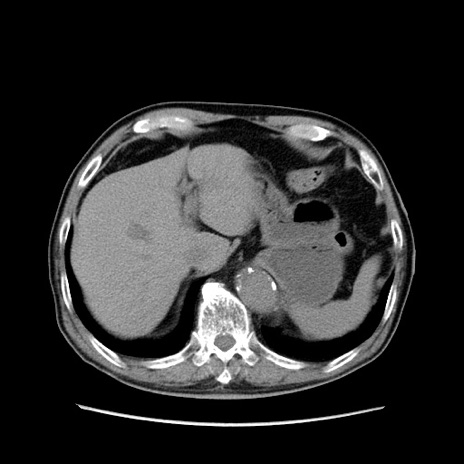

【症例】80歳代男性

【主訴】左側腹部痛、嘔吐

【現病歴】本日早朝より左腹部に痛みあり。昼頃嘔吐認めたため、救急要請。

【既往歴】直腸癌(Mile手術)、胆摘

【身体所見】意識清明、BT 35.9℃、BP 221/93mmHg、SpO2 97%(RA) 、腹部:左ストーマ周囲に限局性の腹部膨隆あり。 膨隆部自発痛・圧痛あり・軟。

【データ】WBC 7700、CRP 0.09